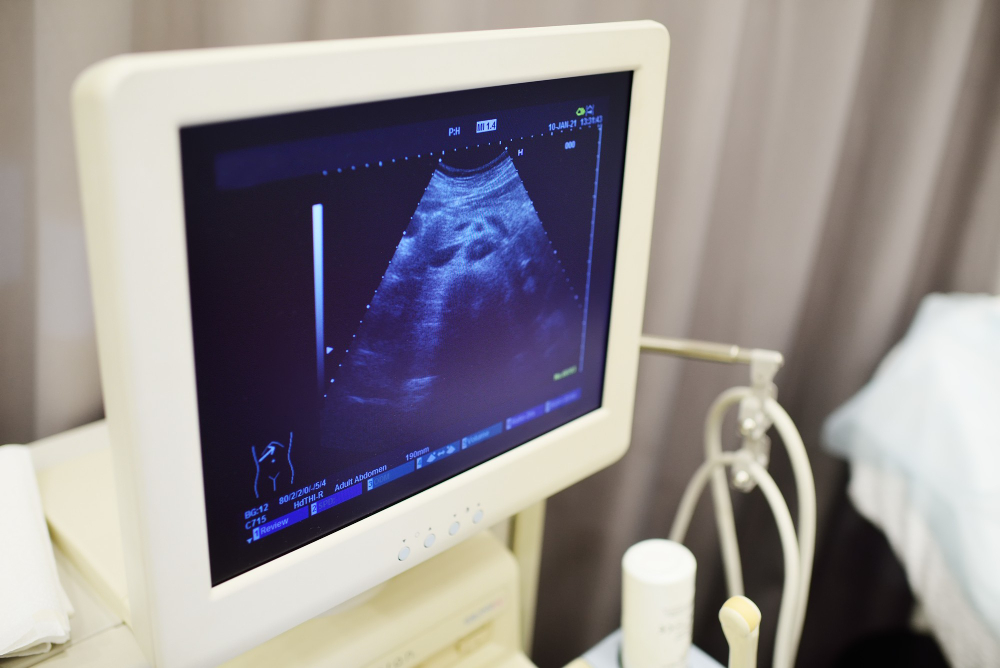

An anomaly scan is a special ultrasound done during pregnancy. It looks at your baby’s body and organs in detail. Usually, this scan happens between 18 and 22 weeks of pregnancy. Doctors use it to check for any physical problems or birth defects. For example, they look at the baby’s heart, brain, spine, and other organs. The scan is safe for both mother and baby.

During the scan, a trained technician or doctor uses a small device called a transducer. This device moves over your belly and sends out sound waves. These waves create pictures of your baby on a screen. The scan is painless and usually takes about 30 to 45 minutes. You do not need to stay overnight. In most cases, you can go home right after the scan.

Before the scan, you may be asked to drink water. A full bladder helps get clearer pictures. During the scan, you will lie on a bed. A gel is spread on your belly to help the device move smoothly. The technician will gently move the transducer over your skin. You may see your baby on the screen. Sometimes, the technician may ask you to change position for better images.